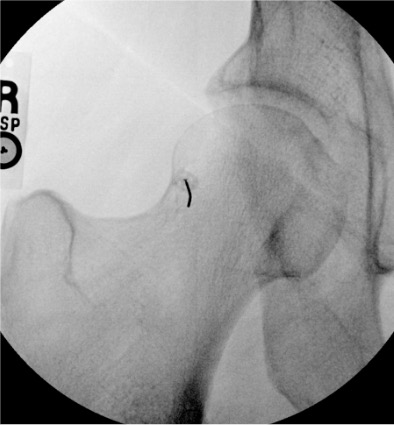

Joint-Specific Access and Injection Protocol

MR arthrogram mixture (all joints): 0.1 mM/mL gadolinium — practical recipe per 14 mL: 0.1 mL gadolinium (e.g., gadobutrol or gadopentetate) + 0.5 mL Omnipaque 300 + 13.4 mL normal saline. The Omnipaque allows fluoroscopic visualization of the injectate.

Needle: 22-gauge spinal needle for all joints. Confirm intra-articular position with 0.5–1 mL Omnipaque 300 before injecting the full arthrogram volume.

Junction of medial femoral neck and head; avoid femoral neurovascular bundle medially

12–14 mL

Intra-articular vs. extra-articular contrast distribution is the key fluoroscopic finding. Intra-articular: contrast flows freely along articular cartilage, fills joint recesses and capsular attachments. Extra-articular: contrast pools in soft tissue planes without joint recess filling — reposition needle before injecting diagnostic volume.

Pattern

Interpretation

Free flow along articular cartilage; fills joint recesses

Intra-articular — proceed with full injection

Soft tissue pooling; irregular tracks in fascial planes

Extra-articular — reposition

Resistance to injection

Extra-articular or needle tip against cartilage/bone — withdraw slightly

Contrast flows into bursa

Bursal communication (rotator cuff full-thickness tear if subacromial; TFCC tear if DRUJ communicates with radiocarpal)